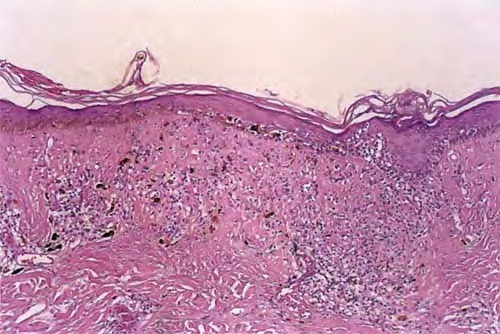

Discoid LE= الذئبة الحمامية القرصية